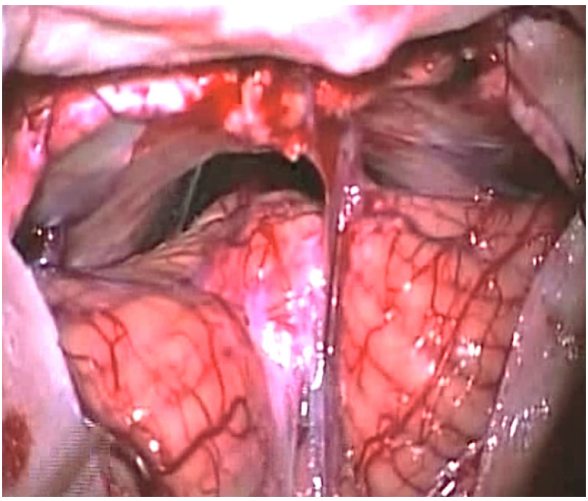

圖1 術中照片顯示Galenic靜脈引流通過小腦上蚓,小腦左側(cè)旁入路暴露的路線